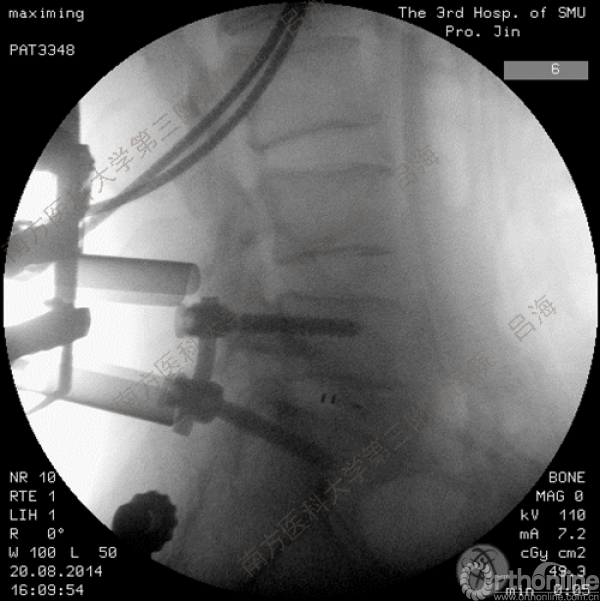

随着社会老龄化进程加快,胸腰椎退行性病变的治疗已经成为脊柱学术界的一个热点话题。MIS-TLIF手术可以治疗多种不同的胸腰椎退行性疾病,南方医科大学第三附属医院吕海教授结合病例为我们一一展示了该术式在治疗不同胸腰椎疾病时的具体手术过程。